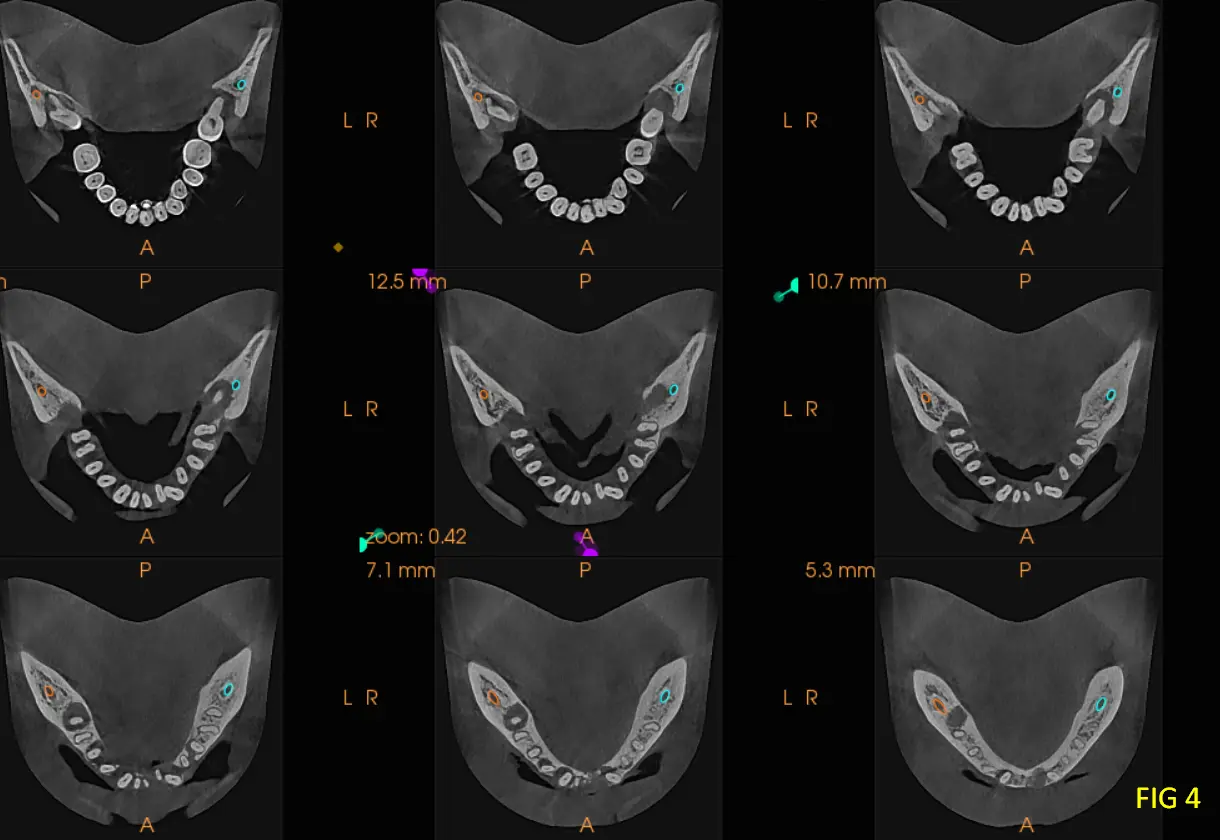

En los cortes transversales, en zona de pieza dentaria 38 (Fig. 4) se visualiza una íntima relación anatómica entre las raíces y el conducto dentario inferior, aspecto relevante para la planificación quirúrgica.